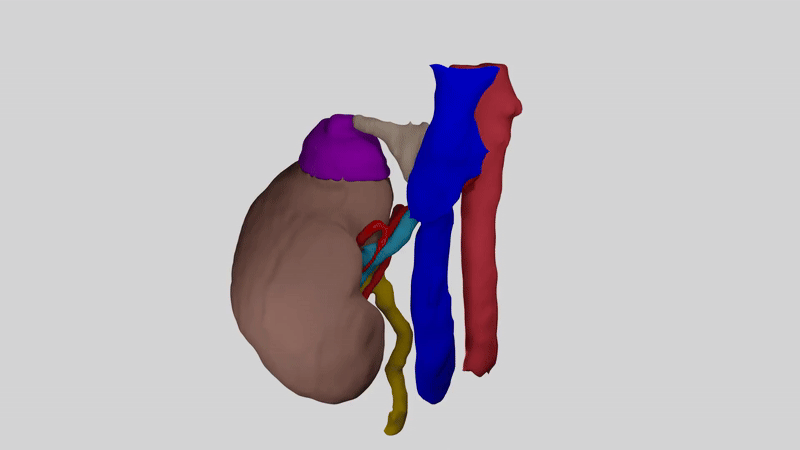

AssistoAR™ създава персонализиран 3D модел на бъбрека и неговата анатомия за всеки пациент.

Моделът показва:

🔹 Точното управление на тумора

🔹 Разклоненията на артериите, които кръвоснабдяват бъбрека

🔹 Каква част от бъбрека може да бъде запазена безопасно

AssistoAR™ създава и специална карта – NaVa (Navigation of Vascularity).

Представете си бъбрека като разделен на цветни зони.

Всяка зона получава кръв от различен клон на бъбречната артерия.

Когато хирургът види тази карта, той може да прецени:

🔹 Кои части на бъбрека се хранят от кои съдове

🔹 Колко от органа може да се запази при операцията

🔹 Как най-безопасно да загубите тумора

Това дава по-точна информация какъв е шансът на бъбреците да бъде съхранен и да помогне на пациента да разбере по-добре своя случай.

Така пациентът разбира как ще протече операцията , а хирургът разполага с индивидуален „пътеводител“ в реално време .